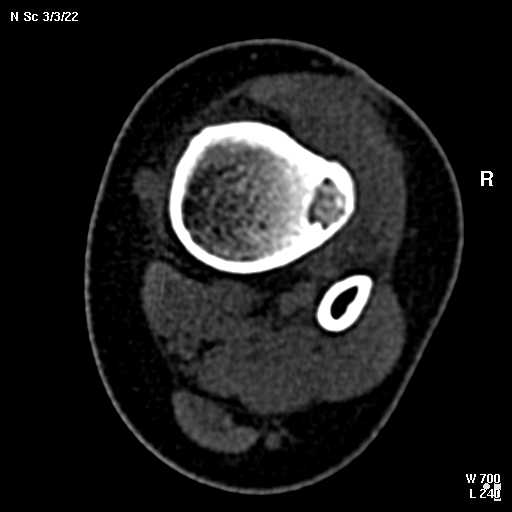

КТ изображения передаю на мой взгляд самые демонстративные. Их любезно записал коллега,

проводивший исследование в другом городе.

Прошу прощения за немного некоректную отправку КТ-снимков но по другому не получается :)